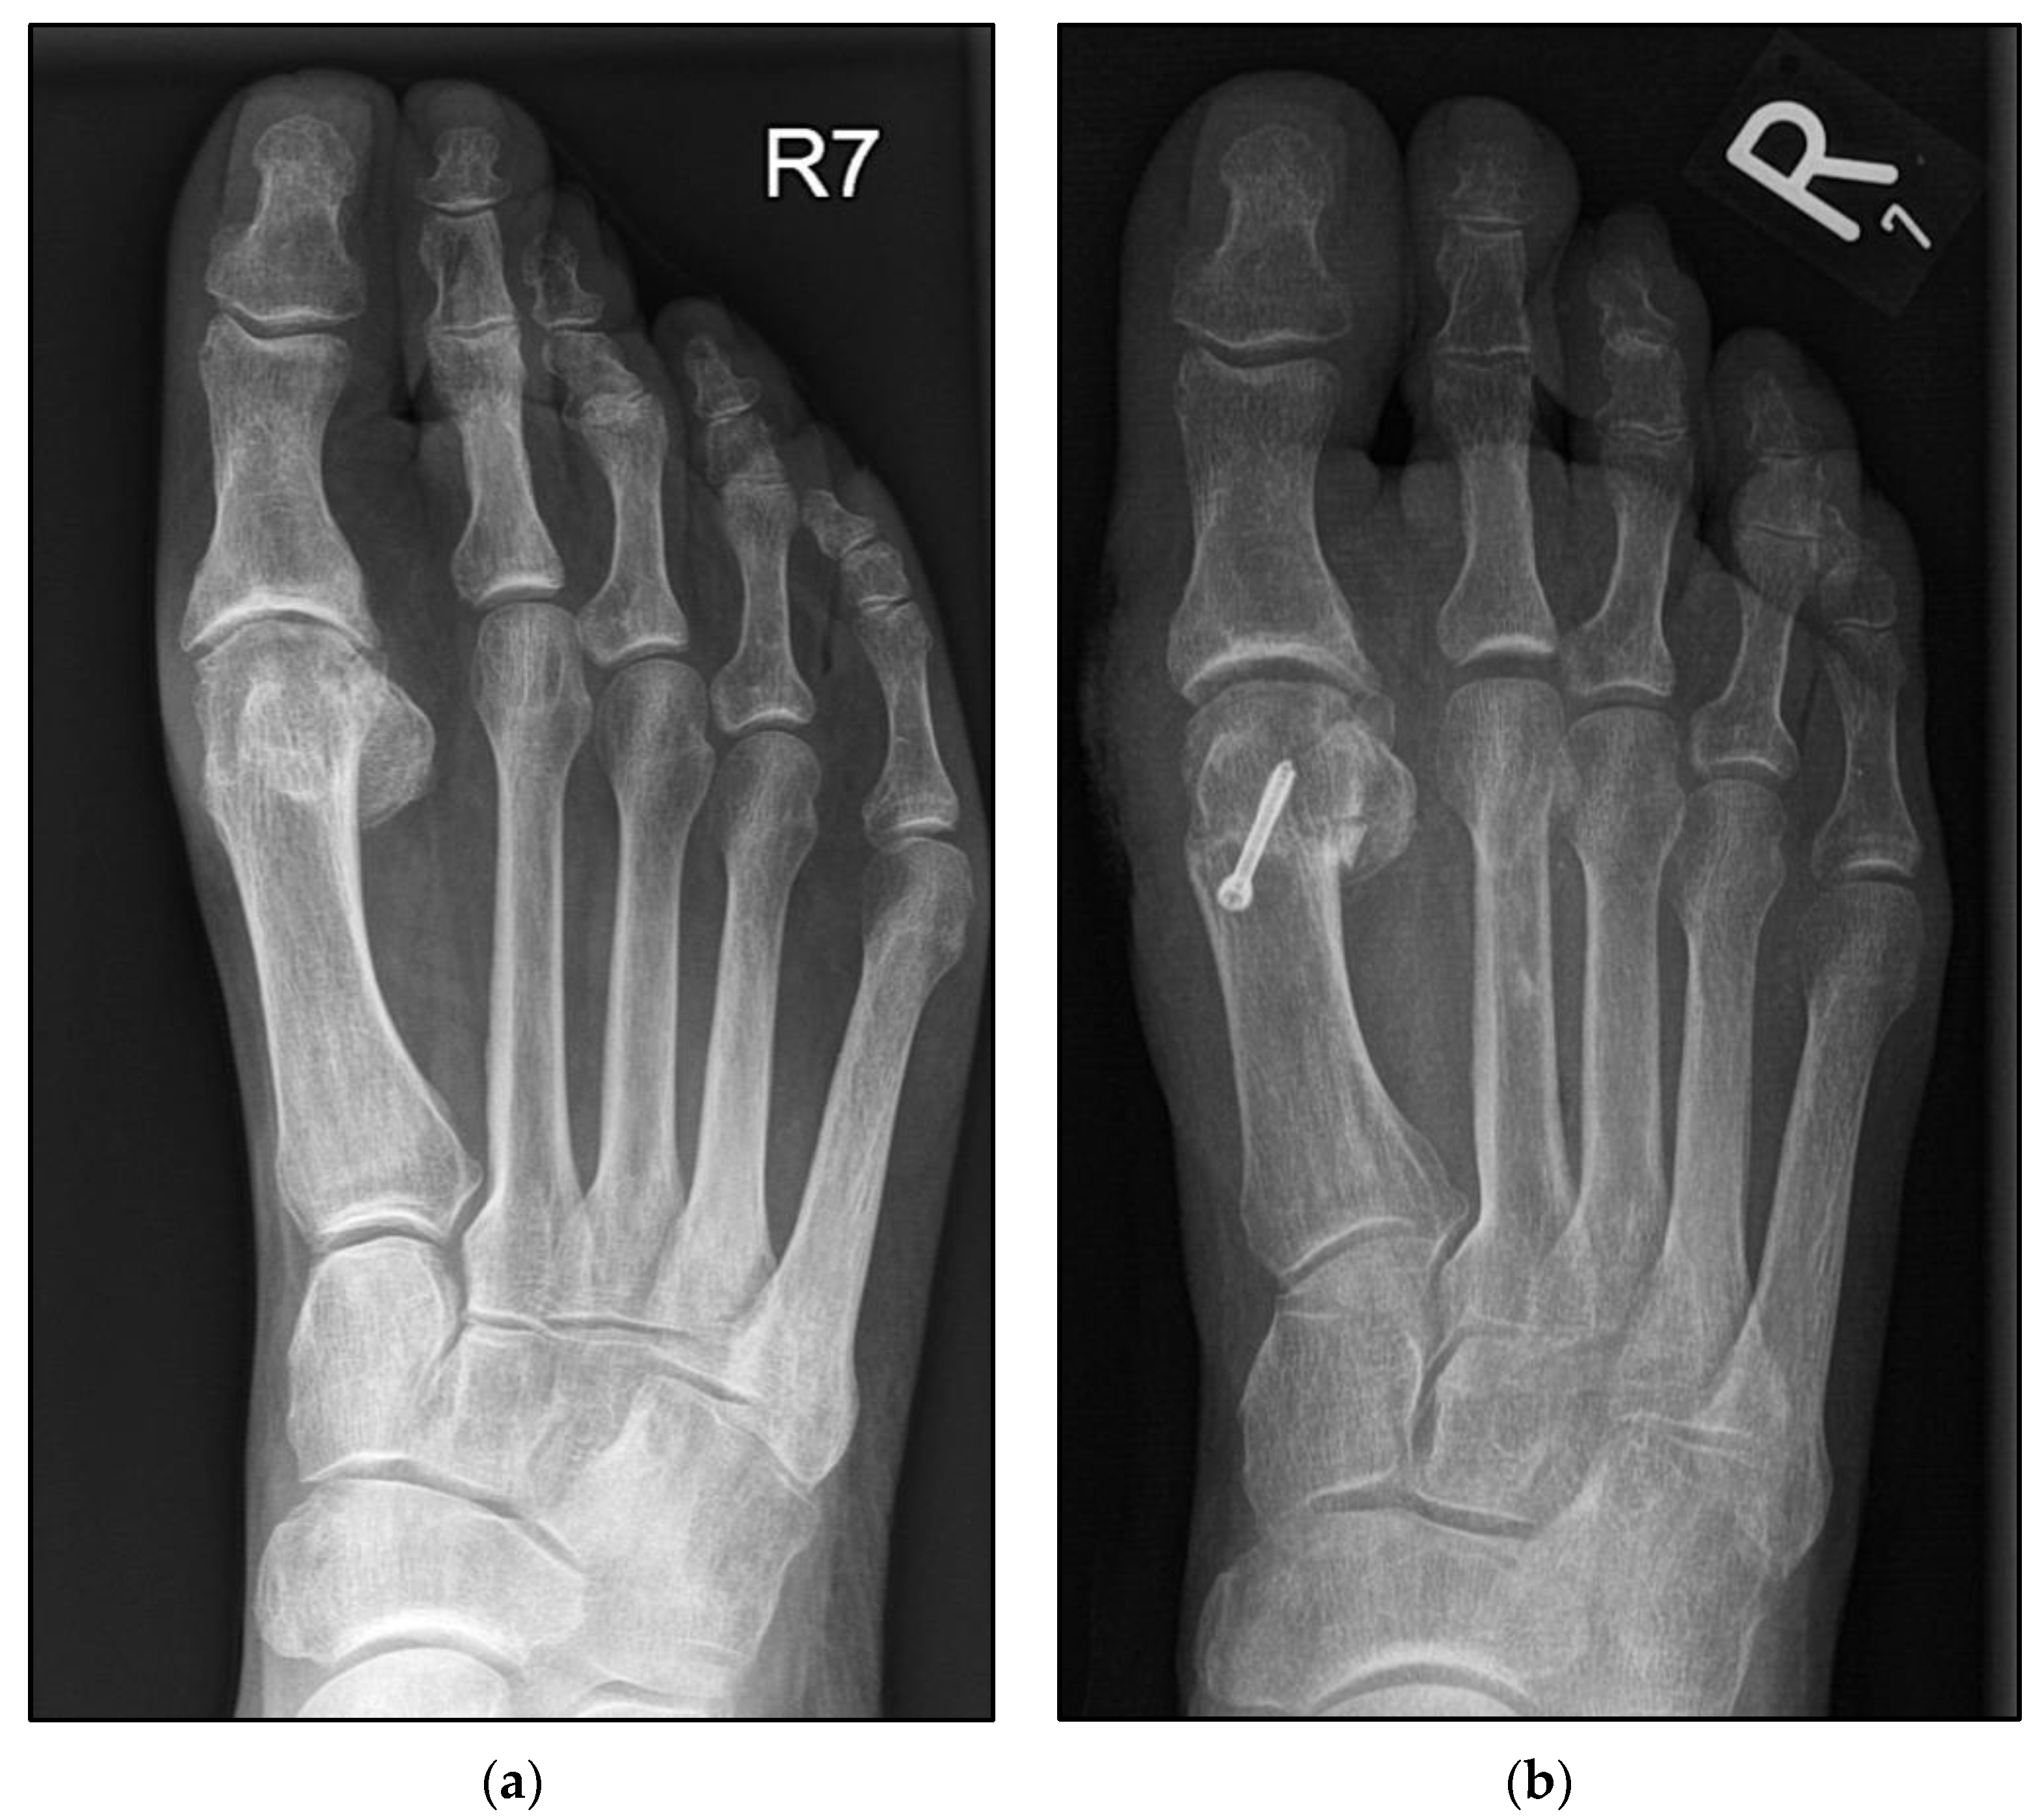

2.3. Surgical Procedure Using the Second Metatarsal as an Example